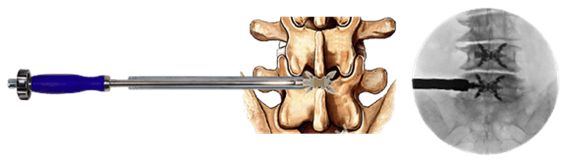

大阪院で新たに始まる先進治療「フローレンス法」について

フローレンス法とは、欧州や南アメリカを中心に導入されている先進的な脊柱管狭窄症の治療です。

これまで脊柱管狭窄症の治療は保存療法で効果がなかった場合は外科手術での対応が主であり、約1週間~2週間の入院が必要でした。

フローレンス法は「入院することなく日帰りで」治療することができる画期的な治療法です。ようやく日本で日帰り脊柱管狭窄症治療ができるようになりました。

保存治療で改善せず、脊椎固定術等の全身麻酔で行われる外科的手術を避けたい患者様にお勧めしています。